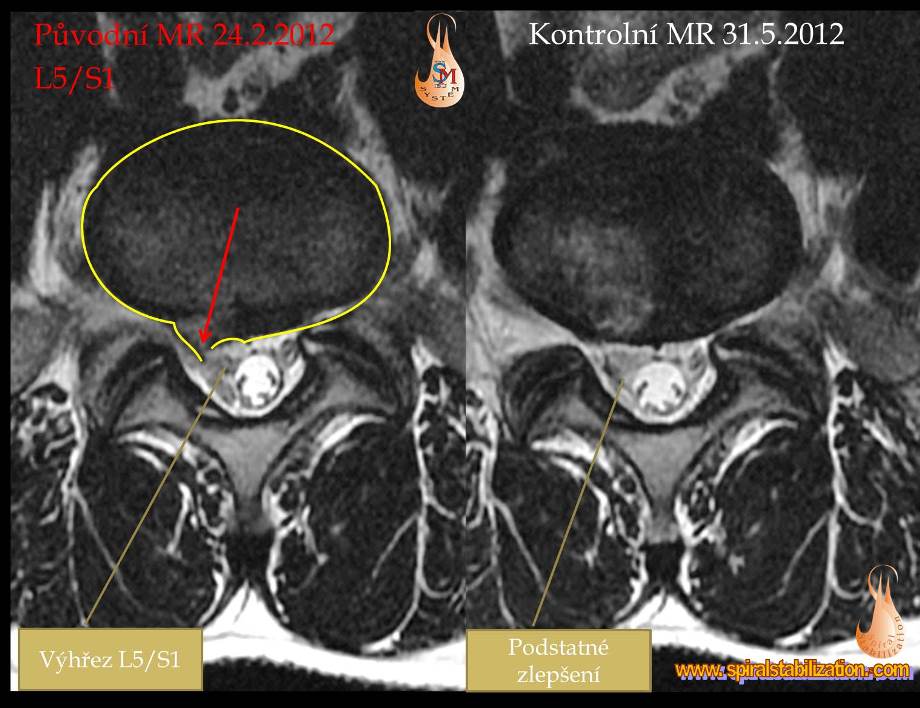

Výsledky hernia L5/S1